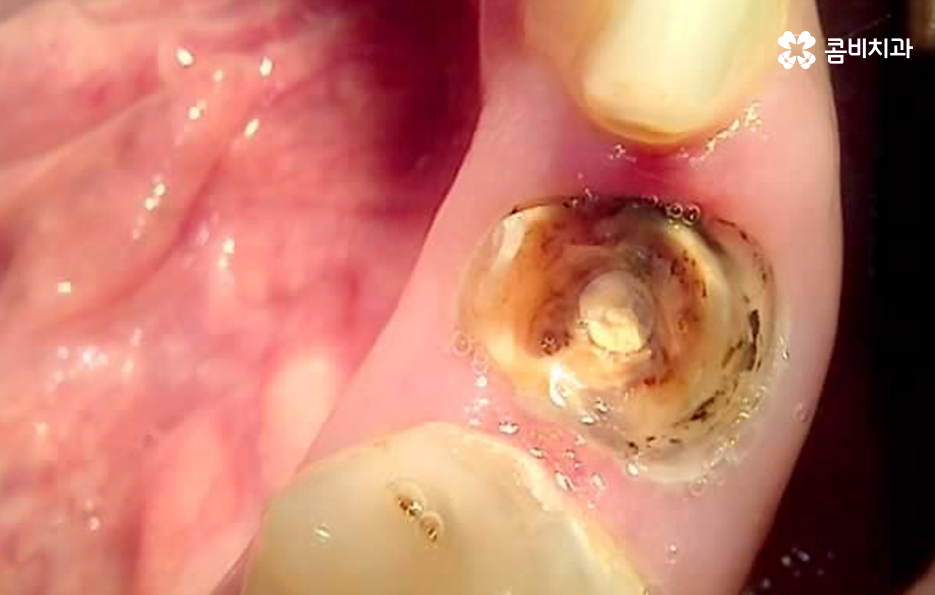

하지만 성인들의 충치 치료는 위 사례들처럼 과거 오래전에 치료 했던 아말감이나 보철물이 떨어지기도 하고 접착제가 약해지면서 2차 충치가 내부에서 진행되어 보철물을 제거하고 내부 상태를 파악해야 하는 경우가 자주 발생되고 있는데요

크고 작은 보철치료를 하다 보면 보철물의 수명이 다하고 교체를 해야하는 시점이 찾아오게 되는데 보철물 내부에서 발생될 수 있는 2차 충치는 기본적으로 주기적으로 검진하지 않고 통증이나 특정 불편함으로 인해 치과에 방문하게 되시면 치료의 적기를 놓치는 경우가 많다고 볼 수 있어요

위 사진처럼 치아의 홈부분에서 시작되는 충치는 칫솔질을 잘하면 성인 이후에 어느정도 예방이 되지만 치아 옆 부분과 잇몸 쪽에 치석이 많이 쌓여 있는 것을 확인할 수 있는데요

치아와 잇몸에 쌓여 있는 치석은 잇몸도 내려앉게 만들 수 있고 치아의 뿌리 쪽 부분이 외부에 드러나게 되어 충치가 치아 하단부에 발생하면 신경과 가깝기 때문에 신경치료로 이어지는 사례도 많이 있어요